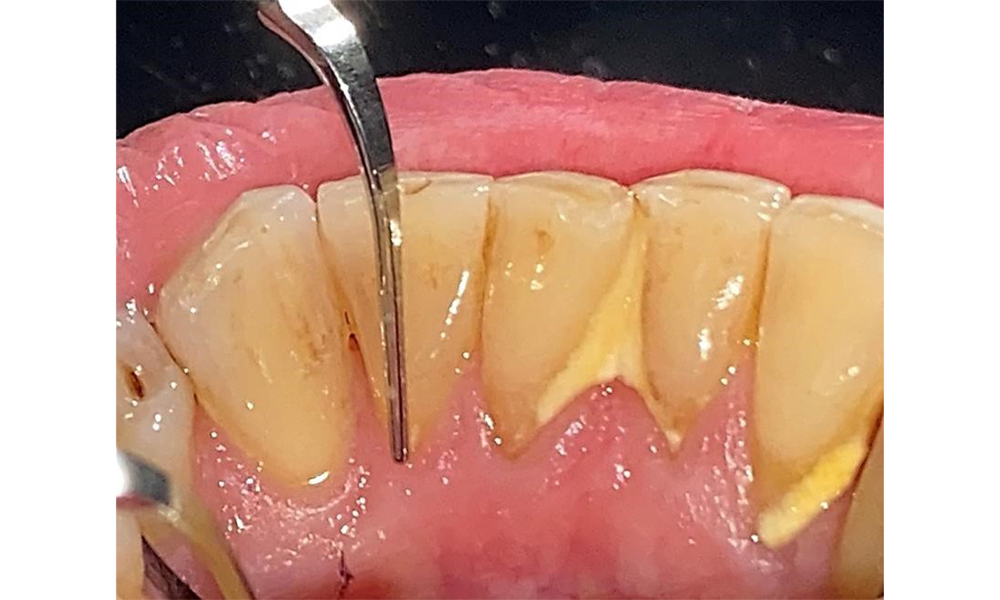

Frontal view with loss of the interdental papillae between 12 and 11.

Fig. 2 Frontal view with loss of the interdental papillae between 12 and 11. © Dr R. Krapf

The patient has stage II, grade B periodontitis (5). At 1 to 3 mm, the clinical probing depths were within the physiological range. Localized probing depths of 5 mm were observed on the mesiopalatal aspects on both 17 and 27. There are generalized recessions of 1–3 mm with partial loss of the interdental papillae (Fig. 2, Fig. 3, Fig. 4)